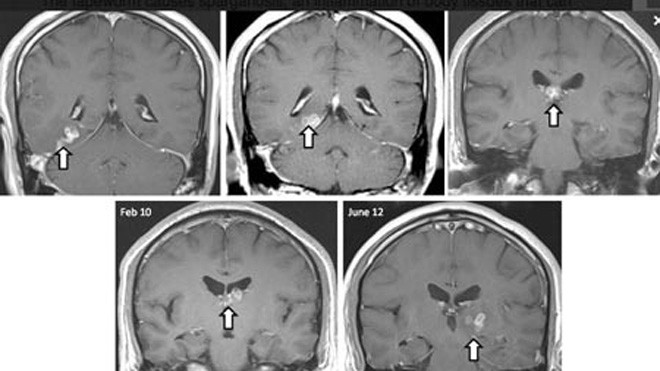

Con sán đã di chuyển 5cm từ bán cầu não phải sang bán cầu não trái của bệnh nhân, gây bệnh sparganum – tình trạng viêm ở mô có thể gây co giật, mất trí nhớ và đau đầu.

Con sán đã di chuyển 5cm từ bán cầu não phải sang bán cầunão trái của bệnh nhân, gây bệnh sparganum – tình trạng viêm ở mô có thể gây cogiật, mất trí nhớ và đau đầu.

Các bác sĩ đã lấy được con sán này ra khỏi người bệnh vàtình trạng của bệnh nhân hiện giờ “nhìn chung là tốt”. Đây là lần đầu tiên bệnhsán Spirometra erinaceieuropaei được báo cáo ở Anh. Mới chỉ có 300 ca bệnh loạinày được báo cáo trong y văn kể từ năm 1953.